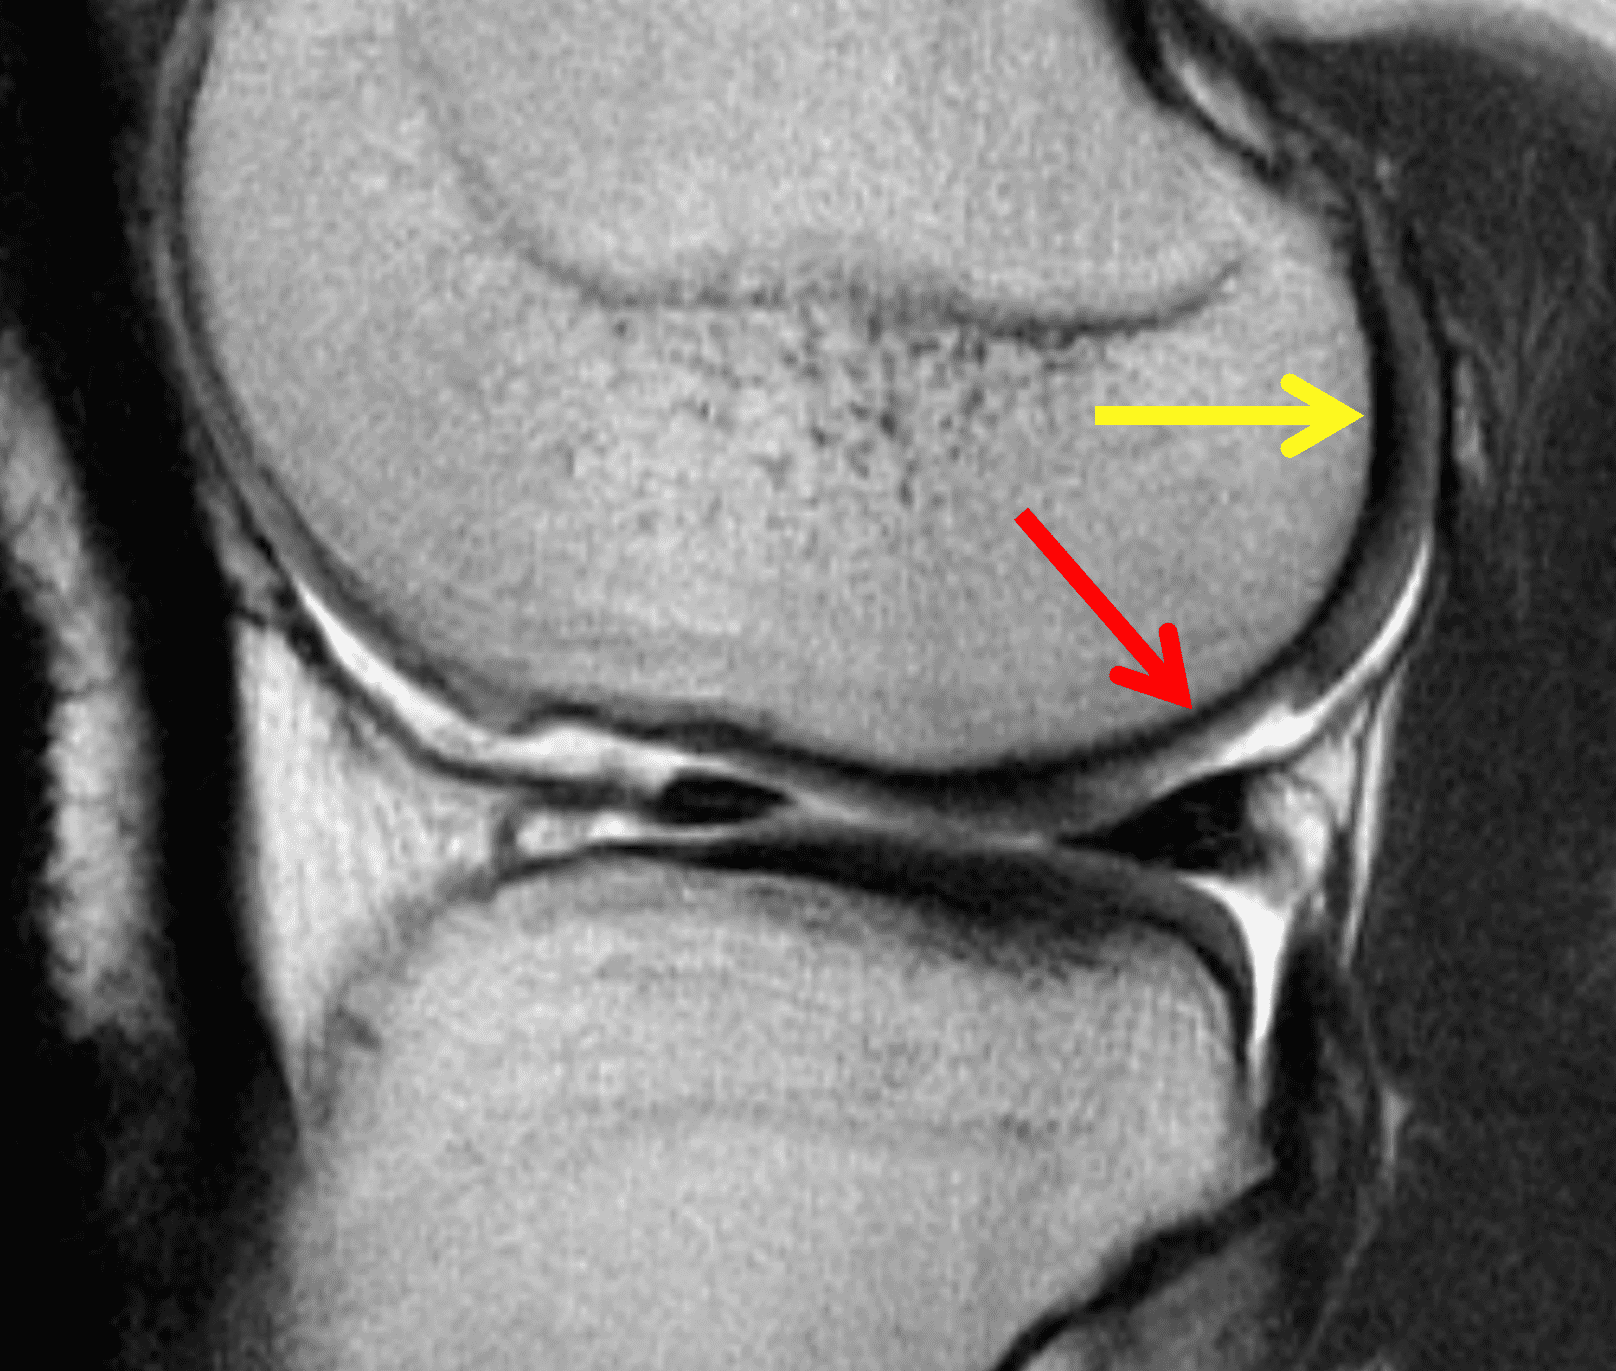

A 32-year-old man suffered a traumatic chondral injury to the medial femoral condyle that was treated with an osteochondral allograft 20 months previously. Representative images from a current knee MRI include (1A) coronal fat-suppressed fluid-sensitive and sagittal (1B) T1-weighted, (1C) proton density-weighted, and (1D) T2-weighted sequences. Are the post-operative MRI findings normal and expected, or abnormal and pathologic? Based on these images, would you characterize the procedure as a success or failure?

Figure 2: (2A) On the coronal image, the margins of the osteochondral graft are faintly visible (arrowheads). Both the graft and underlying bone show mild marrow edema, an expected finding. (2B) The T1-weighted image shows continuity of the marrow in the graft (asterisks) with the underlying bone, indicating osseous integration. A bioabsorbable pin (arrow) used for graft fixation is partly visible. (2C) The proton density-weighted image shows a low signal intensity seam (black arrow) between the native cartilage and transplant, as well as a defect in the subchondral bone plate of the graft (red arrow) where the pin was drilled, both normal findings. (2D) The T2-weighted image shows a smooth, congruent articular surface (arrows), restoring the normal anatomy, and a tiny subchondral cyst. No findings are present to suggest graft failure. The patient’s current symptoms were attributed to pathology elsewhere in the joint (not shown).

Successful osteochondral allograft procedure.

The postoperative imaging appearance of osteochondral allografts is similar to autografts (Figure 2).33 The subchondral bone plate of the donor and recipient sites do not have to match, but the articular surface should be congruent. Grafts that fail to incorporate by one year have a poor prognosis. Persistent marrow edema (beyond 12 months), a thick graft interface containing cysts or fluid, and subsidence of the graft are associated with poor osseous healing and worse outcomes. Extensive host marrow edema and severe synovitis may be a clue to immunologic rejection of the graft (Figure 18).21, 34